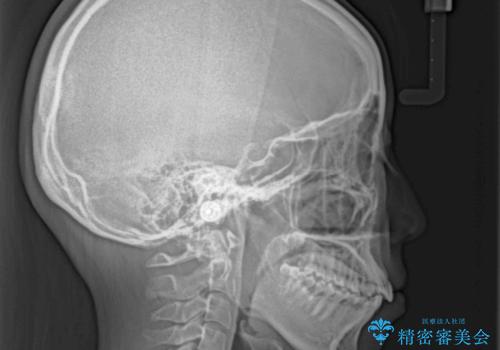

- 口元から飛び出てしまう前歯を気にして来院された患者様です。

上下前歯が嘴のように前方に突出しており、唇が閉じにくい状態であったため、上下左右の第一小臼歯4本を抜歯して、口元の突出感を改善することとしました。